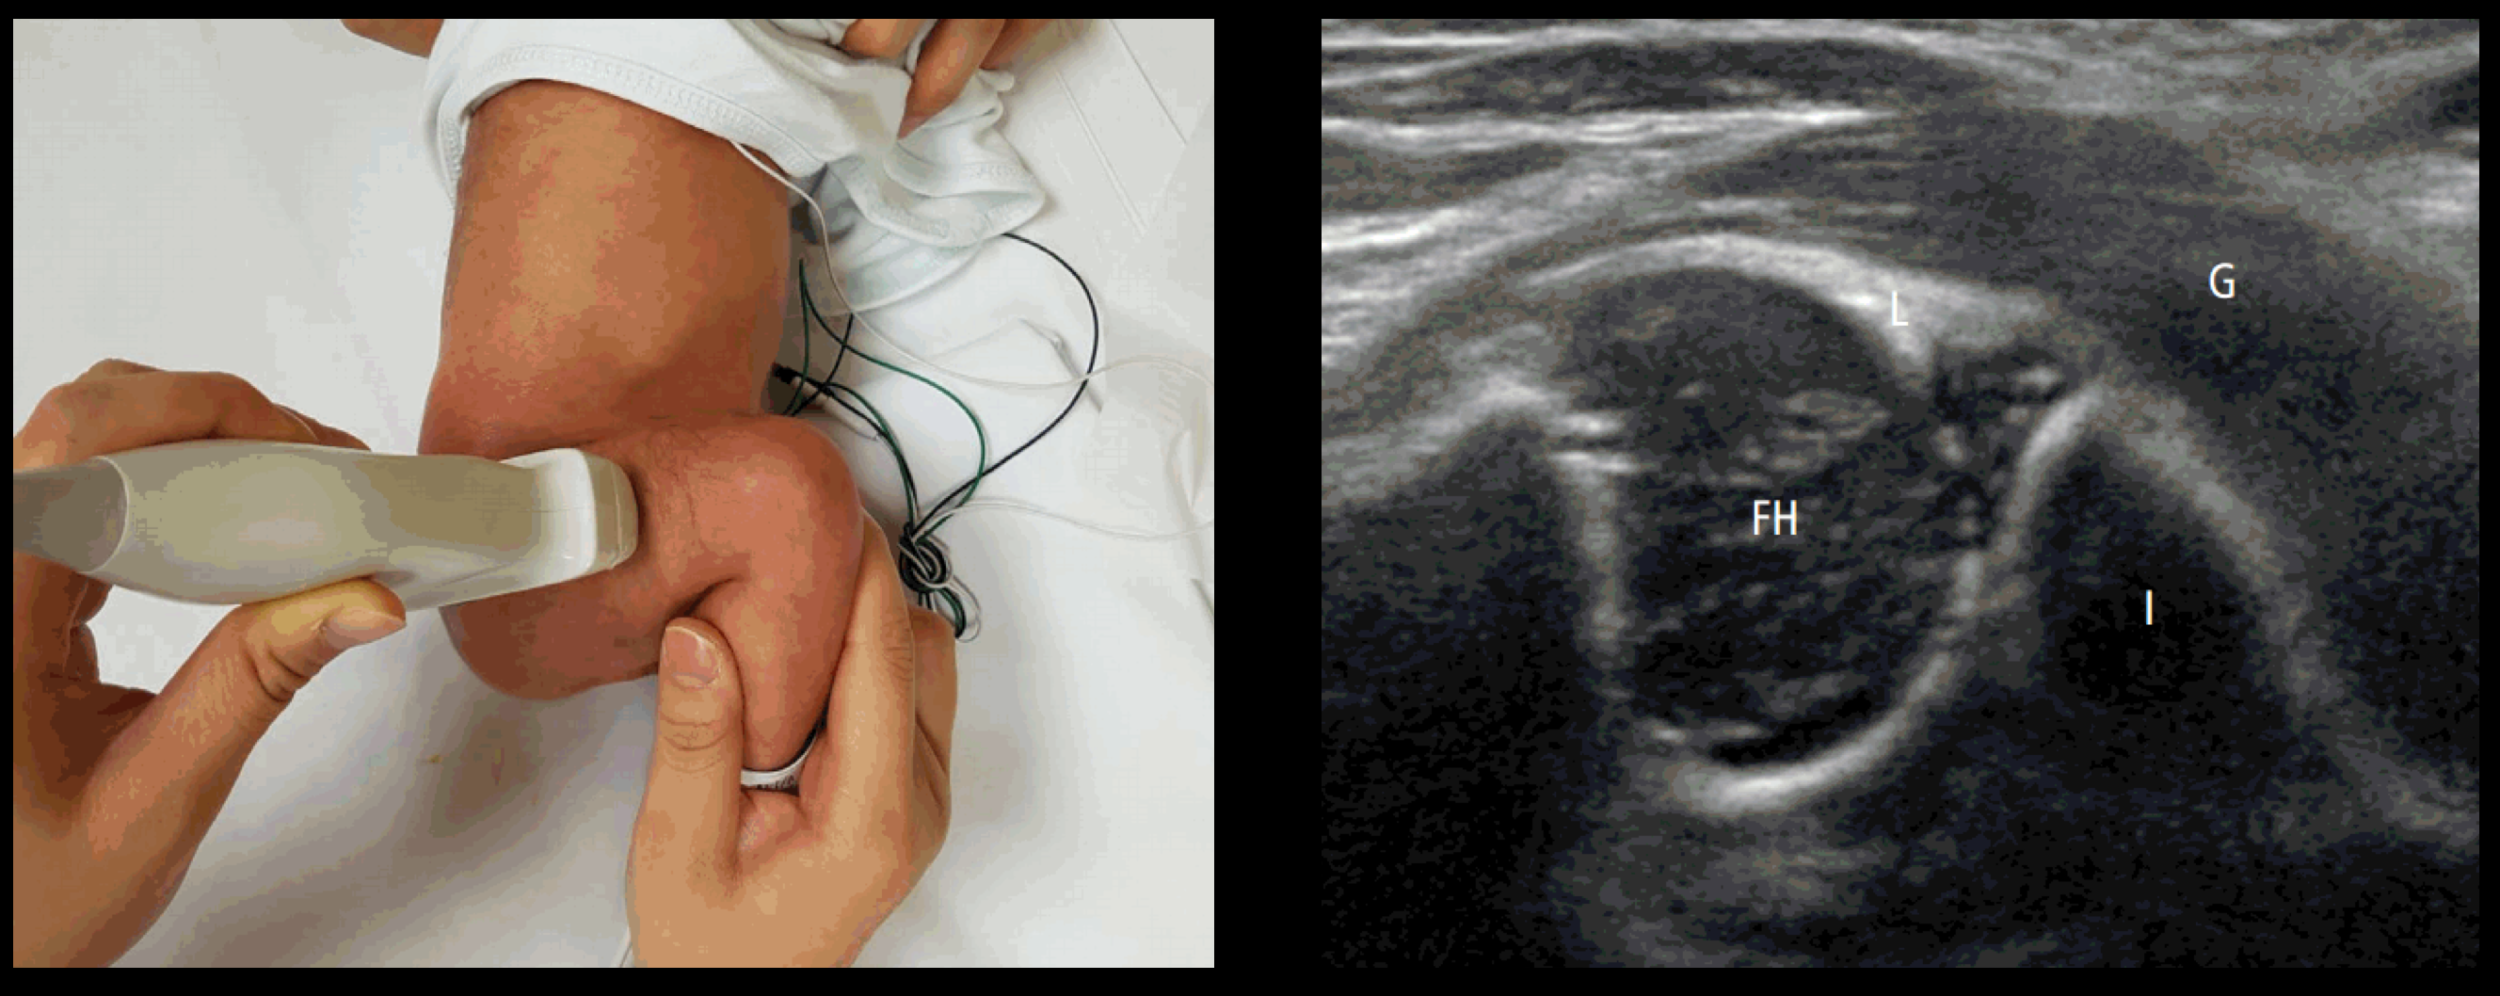

در ابتدا از شما خواسته می شود تا پوشک نوزاد را در آورید و او را به پشت یا یک طرف بر روی تخت قرار دهید. در طول انجام سونوگرافی اتاق تاریک می شود تا پزشک بتواند تصاویر را واضح تر ببیند بنابراین ممکن است فرزندتان گریه کند پس در صورت امکان پیش نوزاد خود بمانید و به او آرامش دهید.

پزشک مقداری ژل را بر روی پوست لگن نوزاد می ریزد و پروب را بر روی آن قرار می دهد و به آهستگی حرکت می دهد. امواج صوتی از پروب و از طریق ژل به مفصل ران منتقل می شود و سپس توسط مانیتور به تصویر در می آید.

در سونوگرافی معمولا هر دو مفصل ران برسی می شود و مدت زمان آن بسته به مهارت پزشک می باشد.